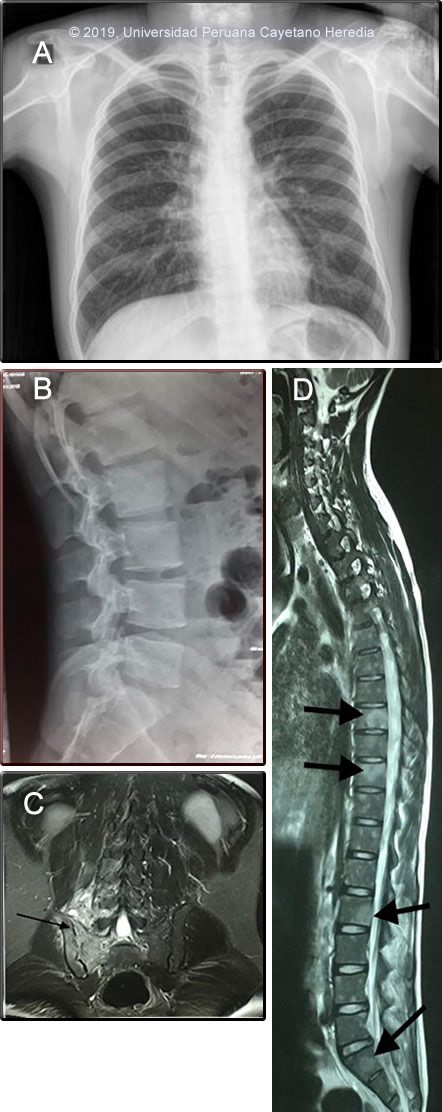

AST / ALT: 70/42 U/L; Alk Phos: 111mg/dL; Bilirrubin: 0.2 HBsAg negative; HTLV-1/2 negative; CD4+ count: 143 cell/mm3; VDRL negative Brucella serology: Negative Chest X ray: normal (Image A). Lumbar spine X-ray: normal (Image B). MRI of sacroiliac joints (SI) shows inflammation and severe erosion of right SI (Image C, arrow) without new bone formation and inflammation and erosion of vertebral bodies without end plate compromise or disk destruction (Image D, arrows) UPCH Case Editors: Carlos Seas, Course Director / Carlos McFarlane, Associate Coordinator UAB Case Editor: David O. Freedman, Course Director Emeritus / German Henostroza, Course Director |

Diagnosis: Extrapulmonary tuberculosis with sacroiliitis and spondylitis

![]() Discussion: A bone marrow biopsy and aspirate from iliac crest showed inflammatory necrosis with histiocytes and lymphocytes without epithelioid differentiation. No evidence of multinucleated giant cells or malignant cells. (Image E) The bone marrow aspirate AFB stain was positive (Image F), and a Gene Xpert MTB-RIF test showed presence of mycobacterial DNA (amplification of IS 6110 and IS 1081) without rifampin resistance (lack of rpoB gene mutations), culture and drug susceptibility testing is pending. Tuberculosis is caused by 3 related organisms Mycobacterium tuberculosis, M. africanum, and M. bovis. Of these, M. tuberculosis is by far the most common [Reichman LB, Hershfield ES, editors. Tuberculosis: a comprehensive international approach. New York: Marcel Dekker; 1993]. The initial route of entry of M. tuberculosis is usually the respiratory tract, followed by hematogenous dissemination. Secondary hematogenous seeding can occur from a silent focus elsewhere in the body (eg gut, kidney). Skeletal tuberculosis is thought to result from hematogenous dissemination from a primary site and occurs 6 months to 3 years after primary infection; but cases associated with relapsing disease have been reported. Skeletal TB accounts for 10 – 35% of all TB cases with 50% being spinal TB (Pott’s disease). Sacroiliac involvement with radiological abnormalities is uncommon accounting only for 1-5% [J Bone Joint Surg Br. 1997 Jul;79(4):562-6] In classical TB spondylitis, the disease process begins in a lumbar intervertebral disc and spreads via the anterior ligament to affect the anterior aspects of the adjacent vertebrae. Destruction of the anterior endplates ensues with anterior collapse leading to a wedge deformity. In our patient, there was compromise of the SI joint with spondylitis and multiple vertebral bodies compromise. Interestingly no compromise of endplates (anterior or posterior) were appreciated which could be related to the related immunosuppression due to HIV infection. However, in some series, a high proportion of patients with bony disease had posterior element involvement (28%), all in association with vertebral body disease. [Spinal Tuberculosis in HIV-Prevalent Setting CID 2018:67]. Sacroiliac tuberculosis is often associated with tuberculous lesions elsewhere, and it primarily originates from a tuberculous psoas abscess or tuberculous spondylitis [see Clin Orthop Relat Res. 1999 Jan;(358):215-22]. No psoas abscess was associated in our case, but as seen on MRI (Image E) likely his SI joint involvement originated from the related spondylitis. Given the broad differential diagnosis and the degree of compromise of the SI joint bone marrow aspirate and biopsy were obtained for cultures for mycobacteria but also for other common bacterial pathogens including Brucella and typhoid. TB sacroiliitis /spondylitis should be differentiated from other infectious disease processes such as pyogenic causes (staphylococcal, gonococcal), typhoid and brucellosis. Non-infectious causes include degenerative and post-traumatic arthritis; inflammatory diseases such as sero-negative spondyloarthropathies, ankylosing spondylitis, psoriatic arthritis, Reiter’s and Behcet’s syndrome, inflammatory bowel disease, rheumatoid arthritis and systemic lupus erythematosus; familial Mediterranean fever with multisystem involvement including arthritis; osteitis condensans ilii; metabolic conditions such as gout pseudogout and hyperparathyroidism; tumors and tumorlike conditions, and pigmented villonodular synovitis [Resnick D, Niwayama G (1995) Osteomyelitis, septic arthritis, and soft tissue infection: organisms. In: Resnick D (ed.) Diagnosis of bone and joint disorders. Saunders, Philadelphia, pp 2461–2485]. Complete destruction of vertebral bodies and the intervertebral disc is seen almost exclusively in infectious processes. Salmonella infection or staphylococcal infections may cause spondylitis and paravertebral abscesses, but concomitant high fever, leukocytosis, and significant systemic illness would be seen. A common feature in these infections is bone remodeling and new bone formation, which was not observed in this patient. Brucellosis, another bacterial cause of sacroiliitis, is endemic in Peru. Spinal brucellosis typically affects the lumbar spine with both lytic and blastic lesions [see Gorgas Case 2001-02]. Malignancy is limited to the vertebral bodies without impinging the intervertebral disc.< The first and second sacral roots pass near the SI joints, with the joint capsule being bordered by the psoas muscle in front and the gluteal and pyriformis muscles behind. Depending on the capsular region involved in the arthritis, the pain may be gluteal or inguinal, mimicking damage to the hip. Frequently, mycobacterial infections of the sacroiliac joint may present as a psoas abscess, and may not be diagnosed until spontaneous drainage occurs in the groin [see Am J Med. 1988 Mar;84(3 Pt 2):622-8]. Buttock pain is invariably present in tuberculous sacroiliitis (as in our patient). The sacroiliac pain can be referred to the groin, posterior thigh, and occasionally below the knee, mimicking pain originating from the lumbar spine, the hip and the lower abdominal quadrant [see J Bone Joint Surg [Am] 58(6):845–849]. There may be signs of femoral or sciatic nerve root irritation if the distended anterior joint capsule comes in contact with the lumbosacral plexus. Confirmed diagnosis of TB spondylitis and sacroiliitis in developing countries is difficult, due to limitations in obtaining representative samples and on the low bacterial load associated with these infections. Diagnostic aspiration or biopsy of the sacro-iliac joint is appropriate when there is minimal bone destruction or at early stages of disease. Bone marrow culture and biopsy is extremely helpful as it will help differentiate from other etiologies (ie. brucellosis, typhoid). Molecular methods, such as the Gene Xpert MTB/RIF allow for faster diagnosis and prompt initiation of treatment. Samples such as bone marrow or urine are appropriate and indicate the disseminated nature of the infection [see BMC Infect Dis 2016;16:514]. Treatment of TB sacroilitis is with standard regimens of anti-TB drugs for at least 9 - 12 months, but more prolonged therapy is recommended in patients with extensive bone destruction and vertebral and paravertebral extension. In TB sacroiliitis, controversy exists as to the need for early surgery. In some series, healing of the infection was accelerated when debridement was done prior to treatment initiation. None of the studies of shorter course chemotherapy have included enough patients with skeletal disease to make any conclusions possible. Patients with acute neurologic deficits within the previous 12-24 hours that suggest extension of disease into the spinal canal should definitely have surgery. Steroids should be considered for very severe paraplegia, especially in the acute stage. Recommendations for a surgical procedure in TB spondylitis include (1)Patients with spinal disease and advanced neurological deficits, (2)Patients with spinal disease and worsening neurological deficits progressing while on appropriate therapy, (3)Patients with spinal disease and kyphosis >40 degrees at the time of presentation and (4)Patients with a cold abscess in the chest wall. Our patient was started on the standard 4-drug initiation regimen of daily isoniazide, rifampin, ethambutol, and pyrazinamide in addition to prednisone for the neurological compromise. Surgical evaluation and discussion of approaches to further joint stabilization are ongoing. ARV treatment was initiated with EFV/TDF/FTC. |